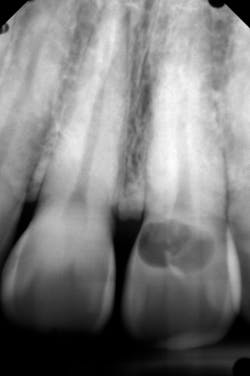

During the past 10 years, I’ve flown all over the US to mentor others in the placement of implants. The recommended compensation to the mentor is between $10,000 and $20,000 per day, funded through patient fees. Generally, the mentee nets more than $10,000 for the day as opposed to paying $10,000 to fly elsewhere for the teaching. These mentorship days are usually scheduled through an implant institute. If you are interested in being a mentor or being mentored, InstituteFaculty.com offers a detailed video explanation. The various clinical cases and figures in this article demonstrate the typical cases that would be included in a standard over-the-shoulder mentorship day. (See figures 1–6.)